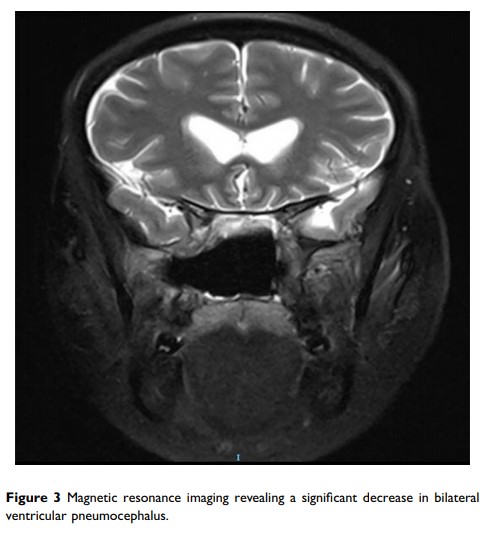

内镜下经鼻入路手术治疗张力性气颅:病例系列和文献综述